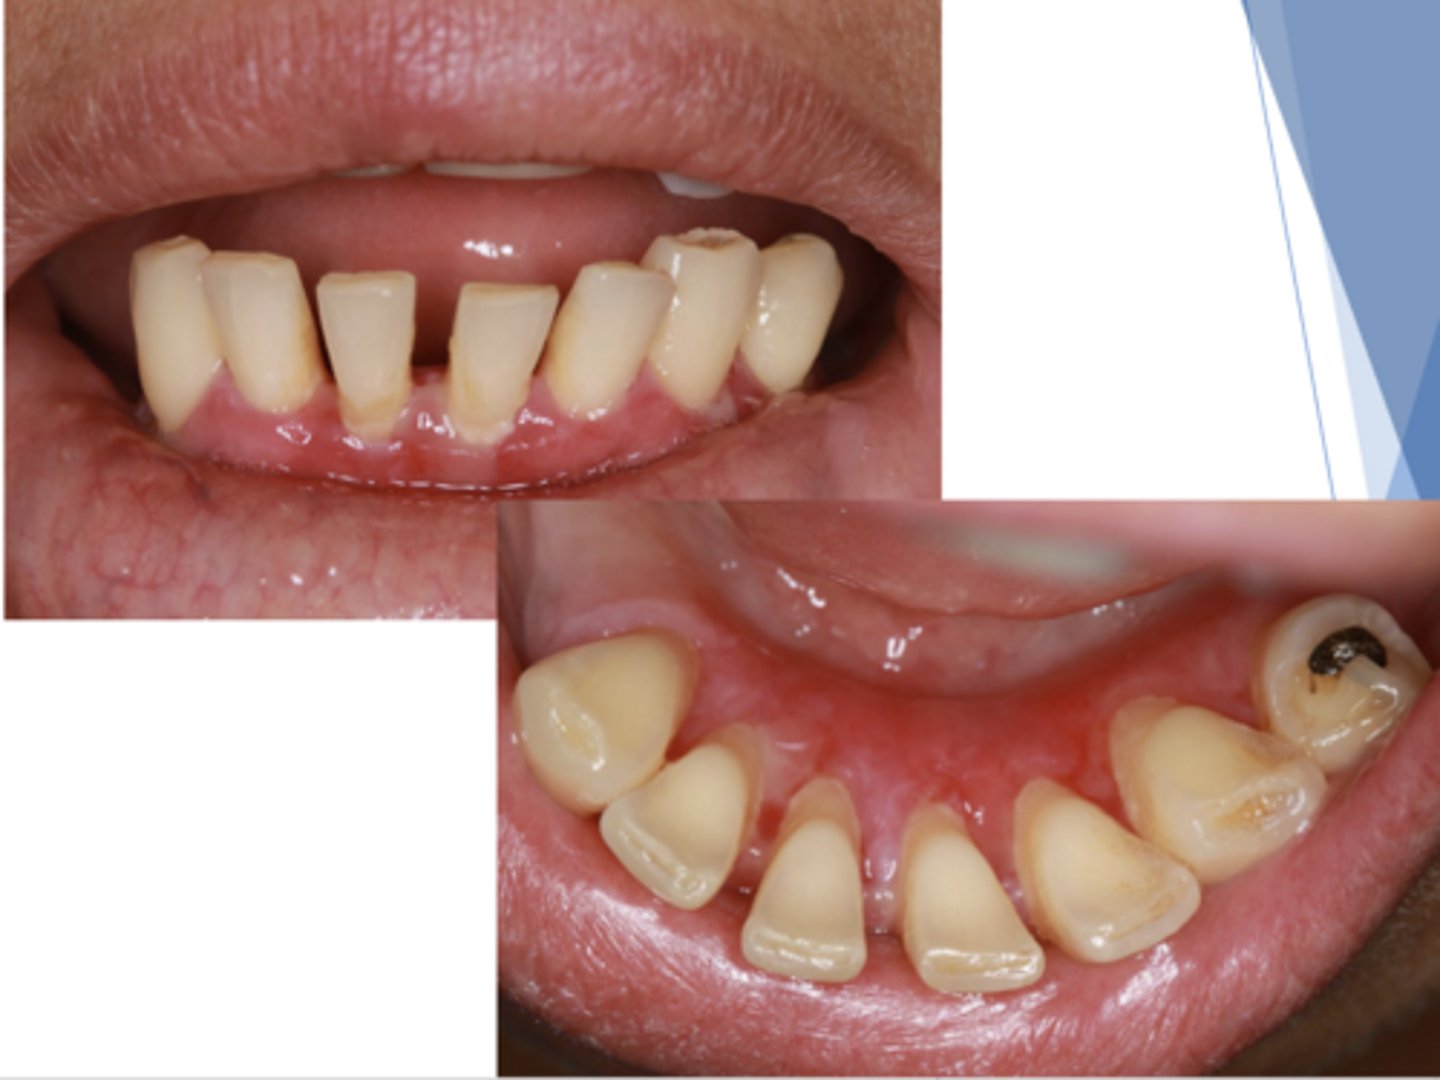

desquamative gingivitis

What is a clinical term to describe a manifestation of what is usually lichen planus, a hypersensitivity reaction, or mucous membrane pemphigoid?

What is gingiva that demonstrates superficial peeling of epithelium characterized by the formation + rupture of mucosal vesicles?

This is the clinical manifestation of which condition?

- Female predilection

- Diffuse, markedly erythematous gingiva

- Generally involves attached tissues

- Sensitivity to spicy foods

nikolsky sign: pressure to affected area with an object/compressed air → new vesicle formation or sloughing

What is a way to clinically diagnose desquamative gingivitis?

What condition?